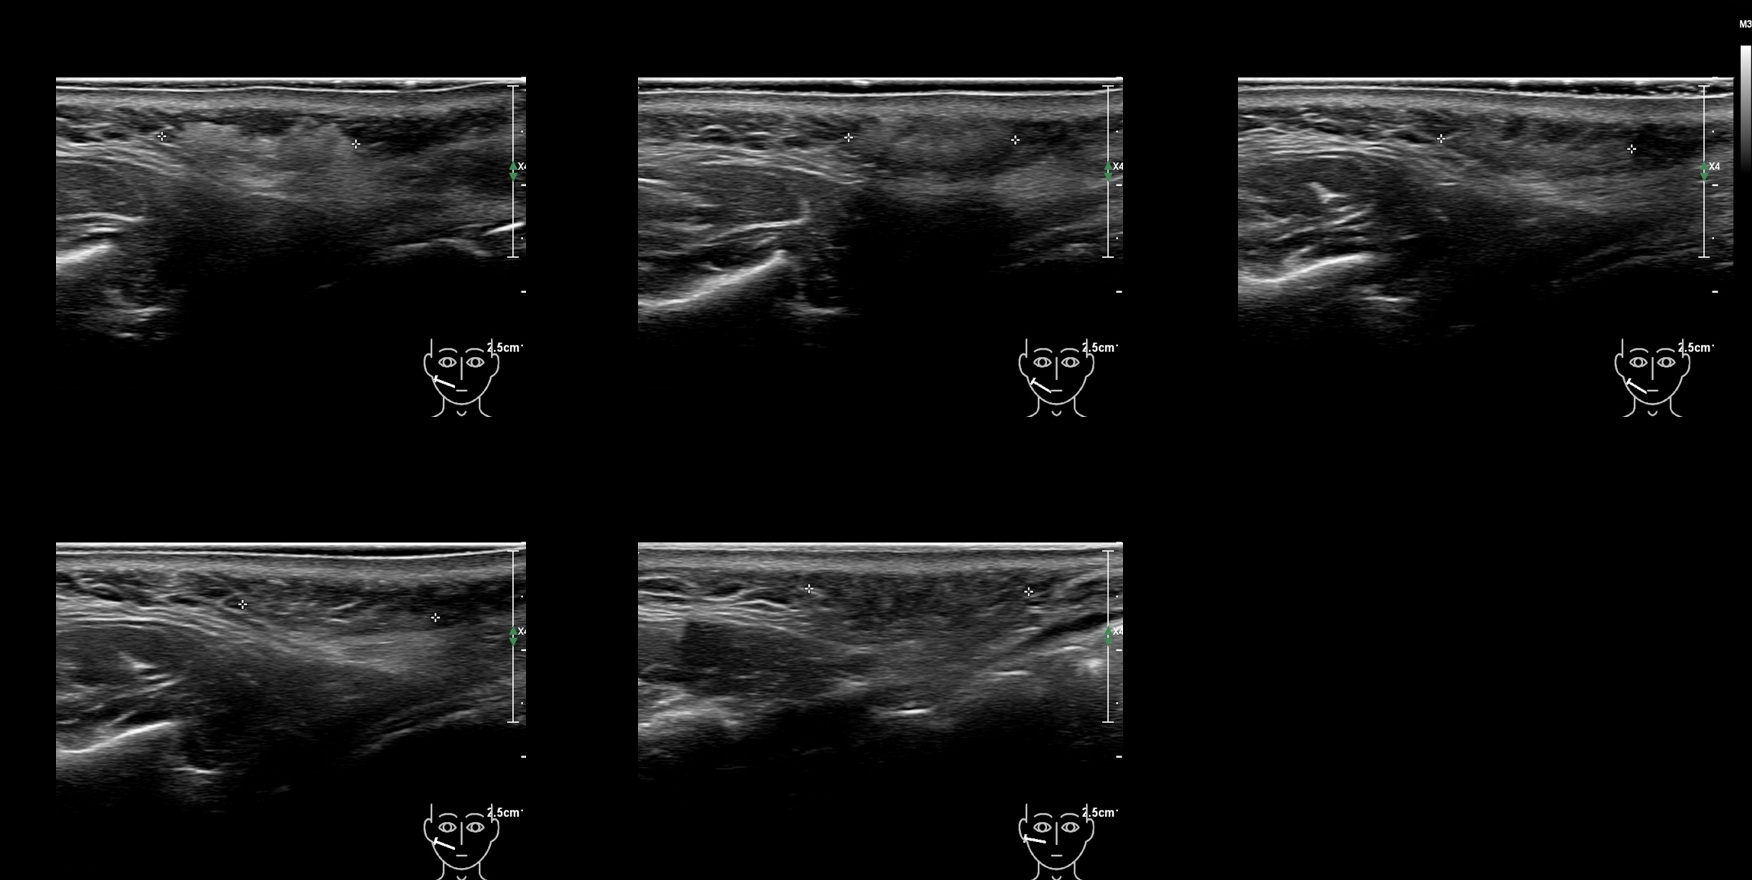

Filler library

CaHa 5a

caha 5b e

caha 60 b e

CaHa 60a

caha 61a

caha 61b e

caha 62a

caha 62b e

caha 63a

caha 63b e

CaHa 69a

CaHa 6a

caha 6b e

CaHa 70a

CaHa 7a

caha 7a e

caha 8a

caha 8b e

caha 9a

caha 9b e

caha0

caha69b e

caha70b e